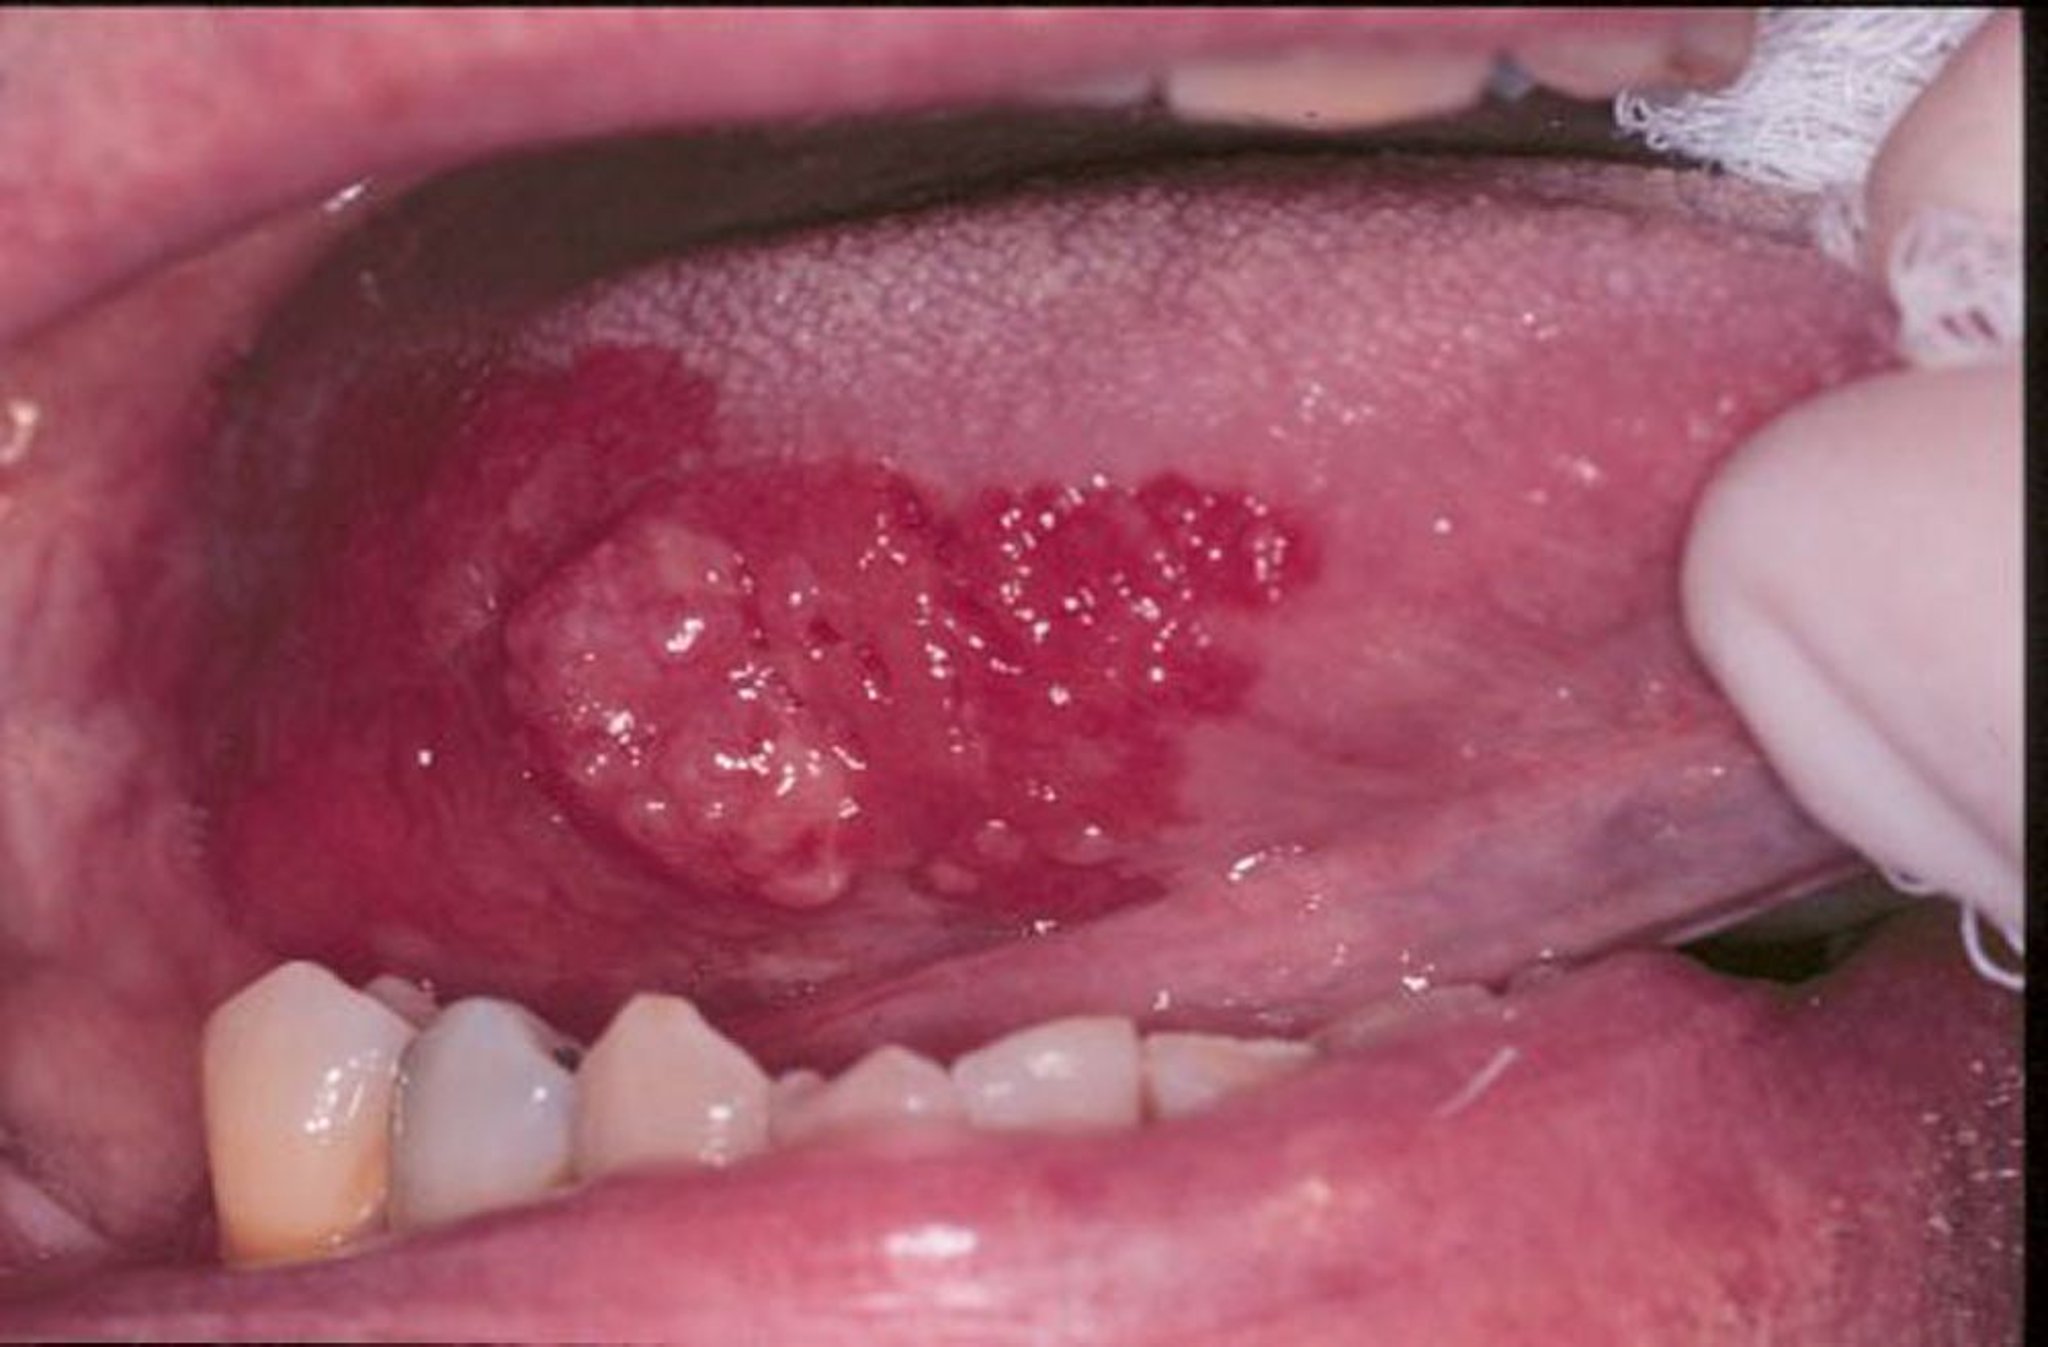

Eritroplasia y carcinoma epidermoide

Eritroplasia es un término general usado para describir lesiones eritematosas planas o aterciopeladas erosionadas, que aparecen en la boca. En esta imagen se observa un carcinoma epidermoide exofítico en la lengua rodeado por un borde de eritroplasia.

Image provided by Jonathan A. Ship, DMD.